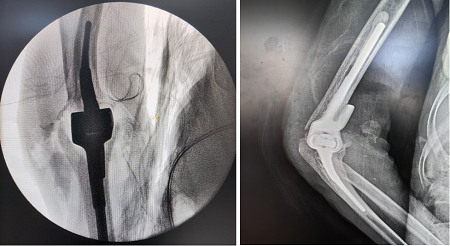

患者是一位70岁女性,因摔伤右肘入住玉溪市人民医院骨外三科。术前X线及CT结果该患者整个右肘关节部位右肱骨远端粉碎性骨折,伤情比较严重。

患者术前关节伤情

在认真分析病情,完善相关术前准备后,骨外三科考虑到患者年龄大,且合并重度骨质疏松,传统的钢板内固定效果不佳,决定为患者实施人工全肘关节置换术。患者手术顺利,术后疼痛明显缓解,肘关节功能明显改善,效果满意。

患者术后关节情况